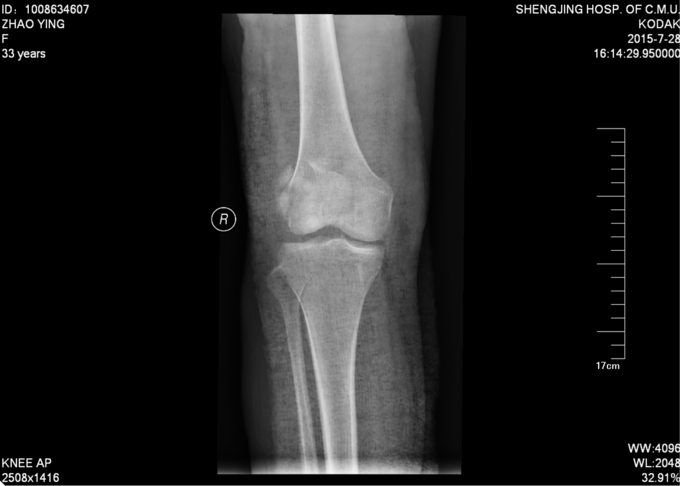

现病史:患者家属代诉于2015年7月23日5点发生车祸,车祸后致右膝部疼痛肿胀活动受限,当时无意识不清,120送至当地医院(辽中县医院),后为进一步治疗,急诊就诊于中国医科大学附属盛京医院,行X线片检查示:右髌骨开放性骨折,急诊给予清创缝合,观察患者病情稳定后,急诊以“右髌骨开放性骨折”为诊断收住我科·。伤来患者无头痛及发热,无咳嗽咳痰,无腹痛及恶心呕吐,饮食睡眠可,大小便正常。

右膝关节已清创缝合,缝合处约10cm不规则创口,右髌骨处软组织肿胀,右膝关节活动受限,右下肢皮肤感觉可,右下肢活动可,。右下肢足背动脉搏动良好,末梢血运良好,皮温正常。

右髌骨开放性骨折 患者急诊行清创缝合后,入院检查后,患者病情平稳,创口1至2天定期换药,观察患者创口愈合,患肢抬高,给予消炎消肿等对症治疗后。入院约一周后创口处无红肿,无渗出,全麻下行右髌骨开放性骨折切口复位张力带内固定术。